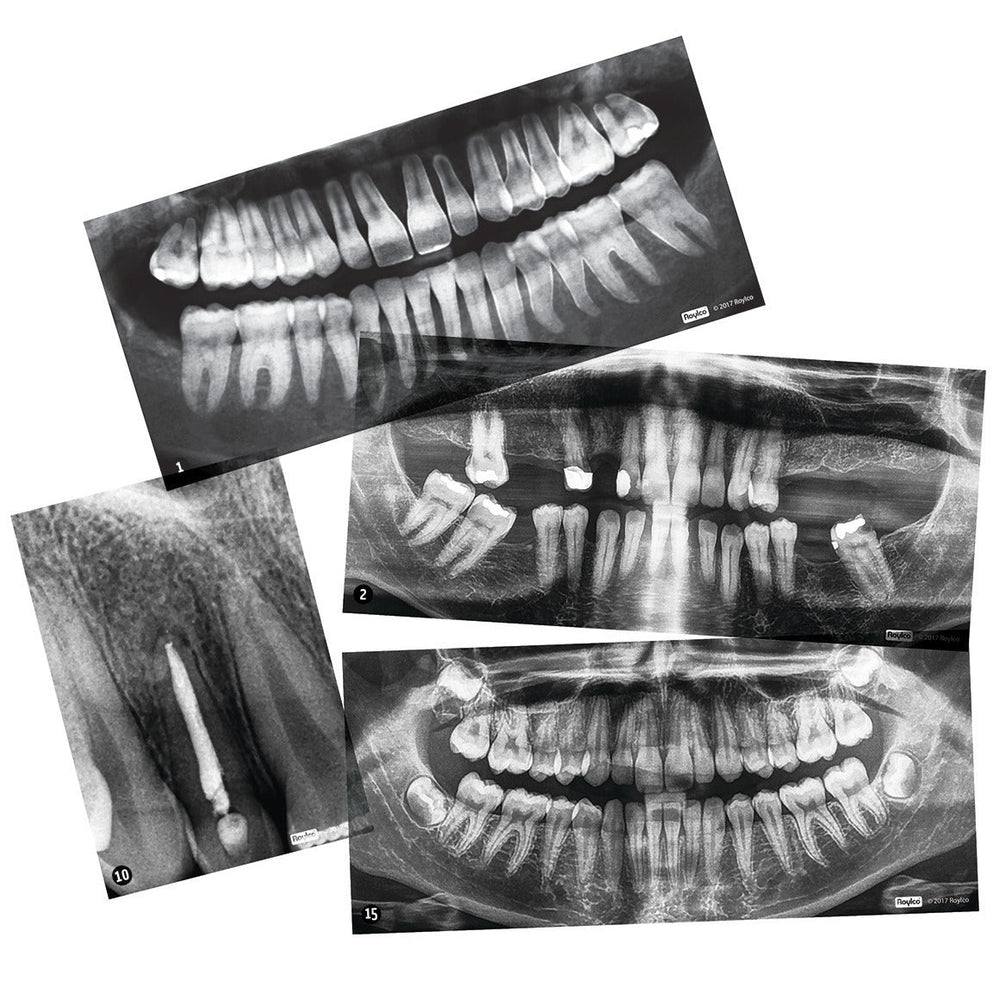

xLearn the importance of taking care of your teeth. These X-rays provide excellent examples of the benefits of good habits and the consequences of bad ones. Includes examples of wearing protective mouth gear, tooth injuries and infections.